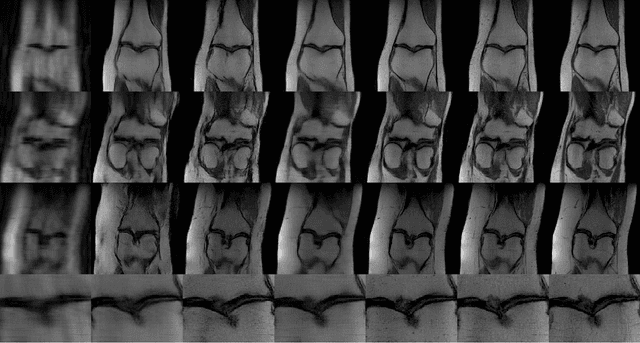

Abstract:Despite the superior diagnostic capability of Magnetic Resonance Imaging (MRI), its use as a Point-of-Care (PoC) device remains limited by high cost and complexity. To enable such a future by reducing the magnetic field strength, one key approach will be to improve sampling strategies. Previous work has shown that it is possible to make diagnostic decisions directly from k-space with fewer samples. Such work shows that single diagnostic decisions can be made, but if we aspire to see MRI as a true PoC, multiple and sequential decisions are necessary while minimizing the number of samples acquired. We present a novel multi-objective reinforcement learning framework enabling comprehensive, sequential, diagnostic evaluation from undersampled k-space data. Our approach during inference actively adapts to sequential decisions to optimally sample. To achieve this, we introduce a training methodology that identifies the samples that contribute the best to each diagnostic objective using a step-wise weighting reward function. We evaluate our approach in two sequential knee pathology assessment tasks: ACL sprain detection and cartilage thickness loss assessment. Our framework achieves diagnostic performance competitive with various policy-based benchmarks on disease detection, severity quantification, and overall sequential diagnosis, while substantially saving k-space samples. Our approach paves the way for the future of MRI as a comprehensive and affordable PoC device. Our code is publicly available at https://github.com/vios-s/MRI_Sequential_Active_Sampling